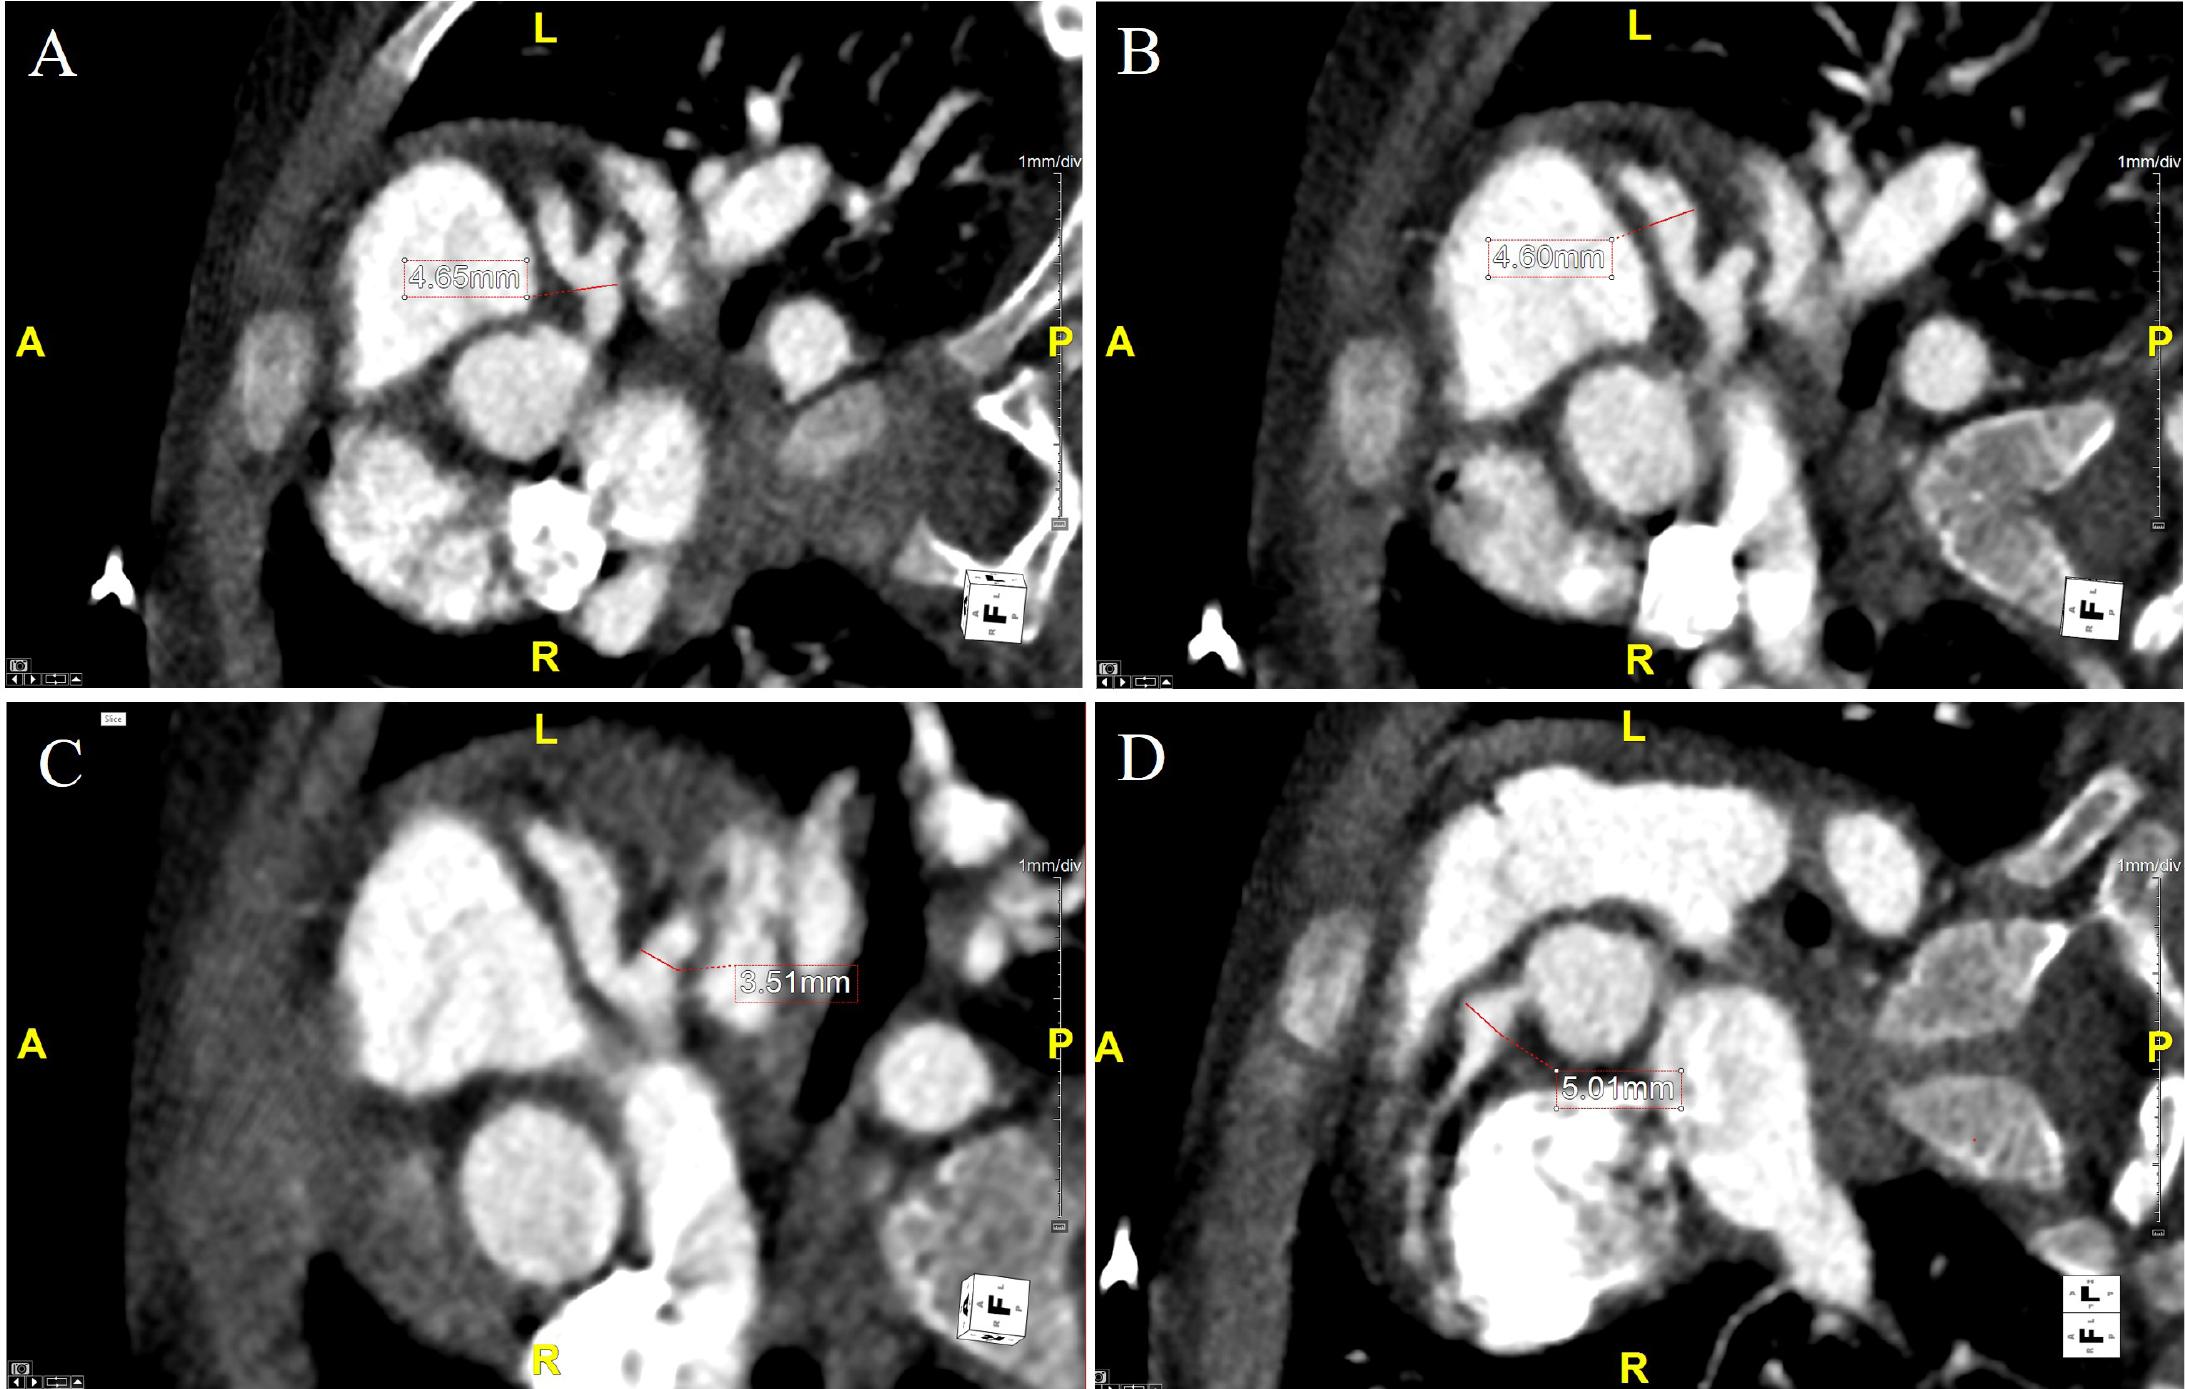

Figure 2